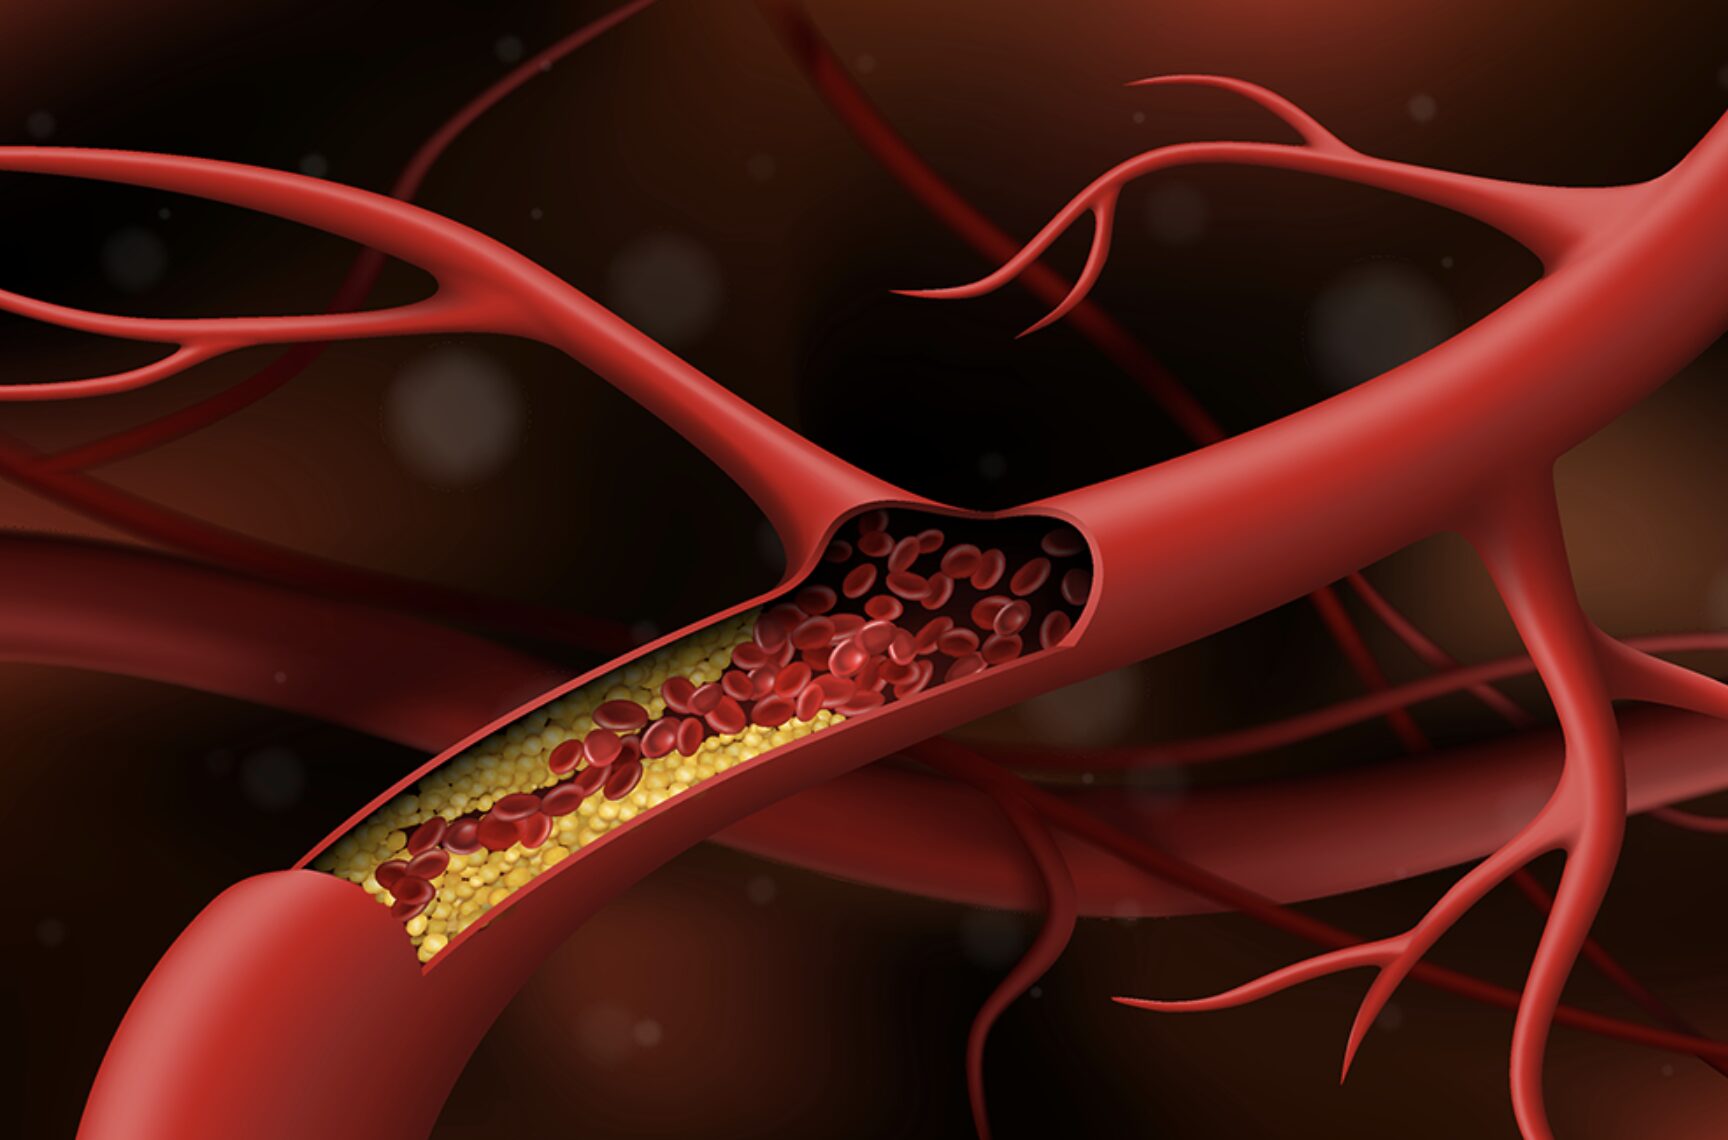

Mối liên hệ giữa tiểu đường và đột quỵ

Tiểu đường được xem là một trong những yếu tố gây đột quỵ. Tuy nhiên, chúng ta có thể kiểm soát bệnh nền và sống chung với bệnh.

Giải mã mối quan hệ nguy hiểm giữa đái tháo đường và đột quỵ